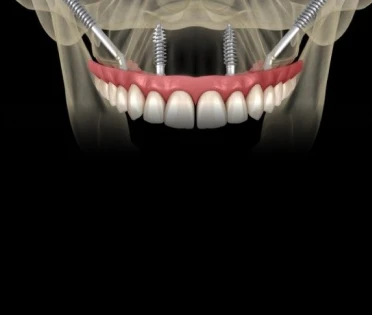

All-on-4 Standard:

Casos ideais com anatomia favorável